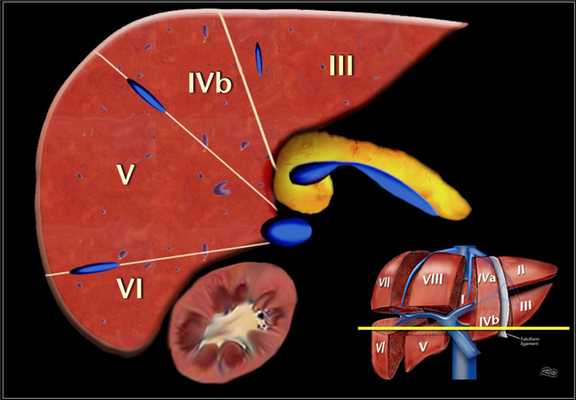

Нумерация сегментов.

Есть восемь сегментов печени. Сегмент IV — иногда делится на сегмент iva и ivb в соответствии Bismuth. Нумерация сегментов по часовой стрелке. Сегмент I (хвостатой доле) расположена кзади. Он не виден на фронтальной проекции. Изображение представлено ниже.

Аксиальная анатомия.

Аксиальное изображение верхних сегментов печени, которые разделены правой и средней печеночной веной и серповидной связкой. Изображение представлено ниже.

Это поперечные изображения на уровне левой воротной вены.

На этом уровне левой воротной вены делит левую долю в верхних отделах (II и IVa) и нижних сегментов (III и IV в).

Левая воротная вена находится на более высоком уровне, чем в правая воротная вена. Изображение представлено ниже.![5]()

Аксиальное изображение на уровне правой воротной вены. На данном срезе воротная вена делит правую долю на верхние сегменты ((VII и VIII) и нижние сегменты (V и VI).

Уровень правой воротной вены ниже уровня левой воротной вены. Изображение представлено ниже.![6]()

Аксиальное изображение на уровне селезеночной вены, которая находится ниже уровня правой воротной вены, видна только в низко лежащих сегментах. Изображение представлено ниже.

Как разделить печень на сегменты при аксиальных кт изображениях.

- Левая доля: латеральный (II или III) vs медиальный сегмент (IVa/b)

- Экстраполировать (провести воображаемую) линию вдоль серповидной связки до места слияния левой и средней печеночной вены в нижнюю полую вену (IVC).

- Левая против правой доли — IVA/B vs V/VIII

- Экстраполировать линию от ямки желчного пузыря кверху вдоль средней печеночной вены к НПВ (красная линия).

- Правой доли: передний(V/VIII) vs задний сегмент (VI/VII)

- Экстраполировать линию вдоль правой печеночной вены к НПВ книзу до латерального края печени (зеленая линия).